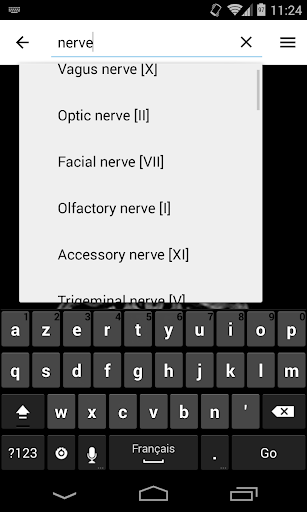

- Mudah menemukan struktur anatomi berkat pencarian indeks

*Temukan bagian anatomi Anda dengan lebih mudah berkat fitur pencarian baru yang lebih intuitif dan canggih